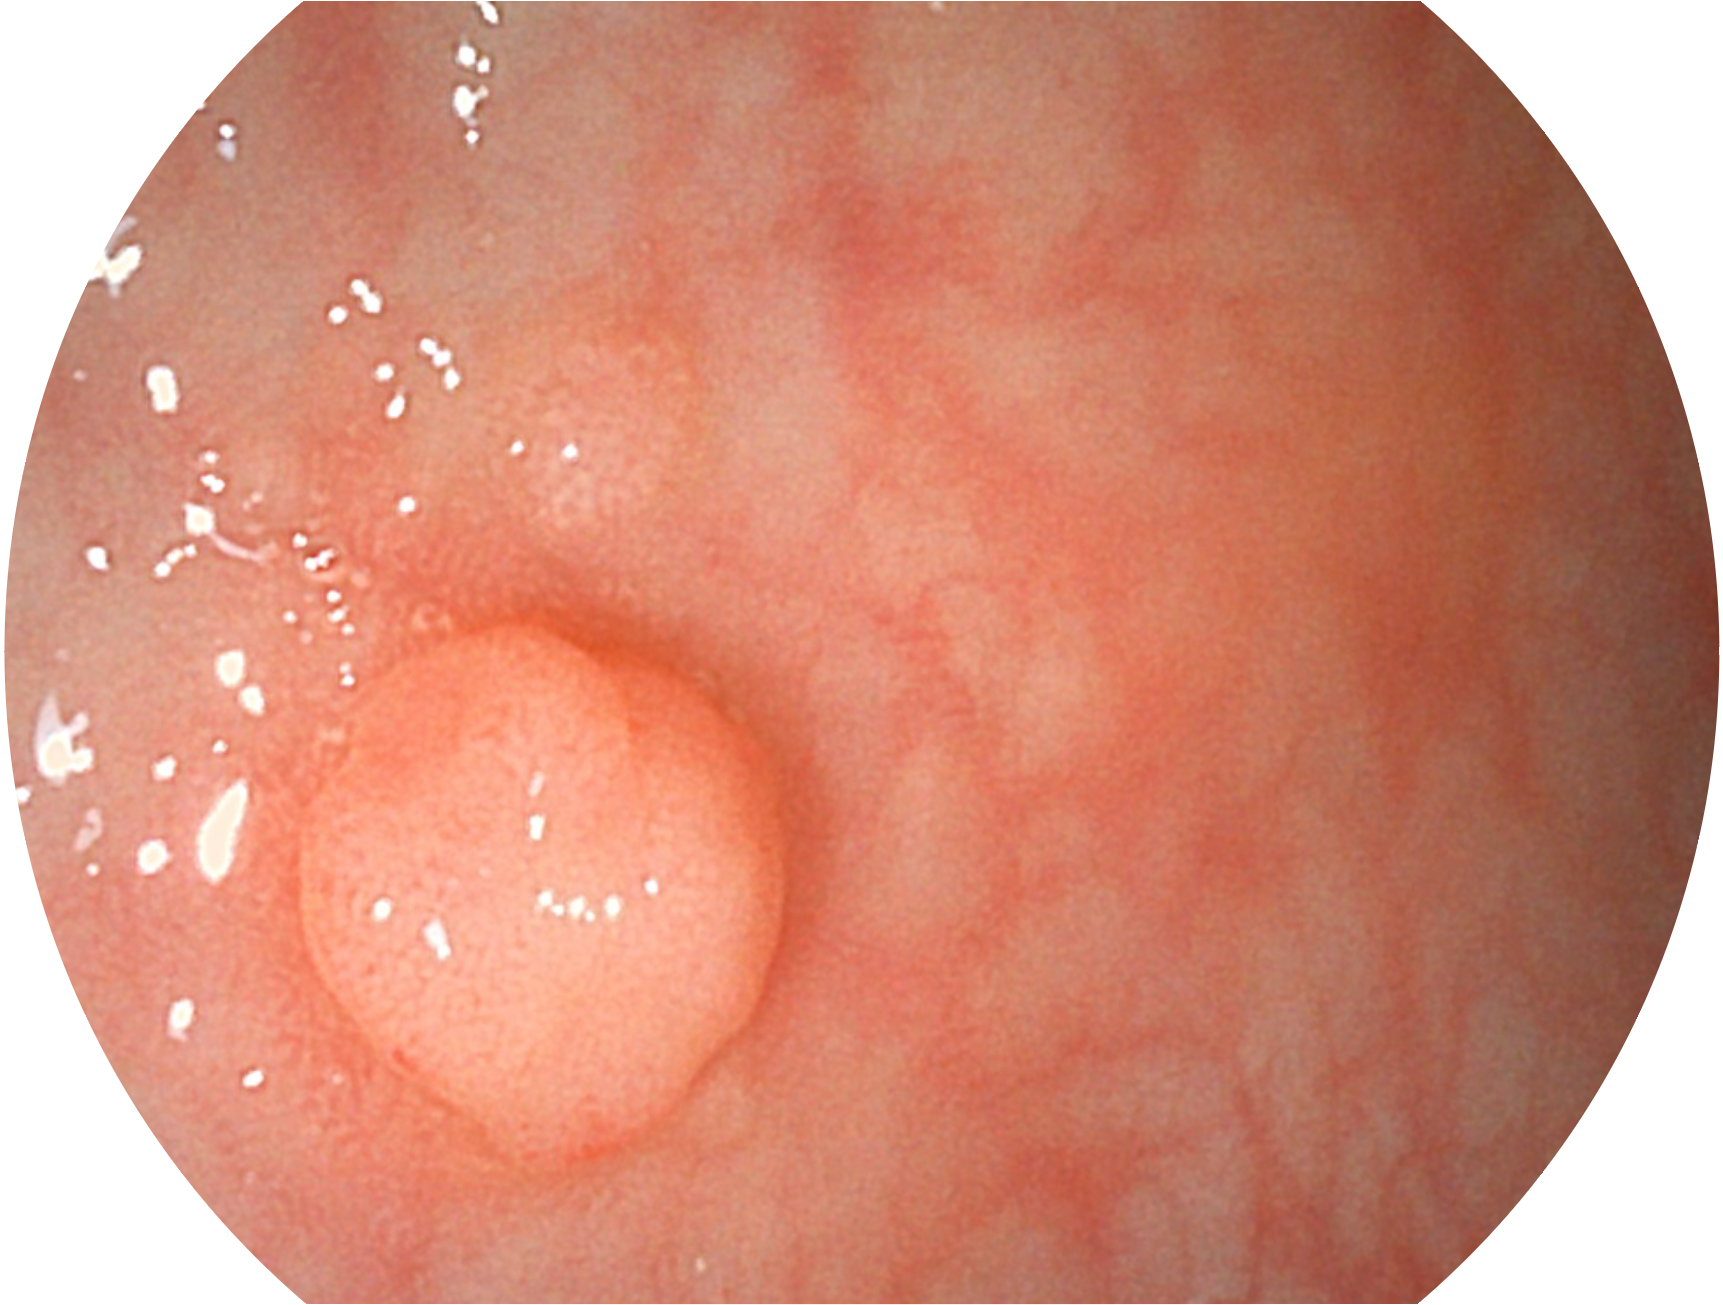

開立新開發(fā)的內(nèi)鏡染色技術(shù),主要是基于多波長LED 光源的開發(fā),VLS-55Q 四波長LED 光源是由四個不同顏色的LED光按照相應(yīng)照明模式所規(guī)定的特定發(fā)光比例進行合束后形成,合束后形成的照明光的光譜由紅光、綠光、藍光及藍紫光這四個不同的波段范圍構(gòu)成。具有更高光譜自由度,通過光譜比例的控制,實現(xiàn)了聚譜成像技術(shù),英文全稱為“Spectral Focused Imaging, SFI”,縮寫為“SFI”和光電復(fù)合染色成像技術(shù),英文全稱為“Versatile Intelligent Staining Technology, VIST”,縮寫為“VIST”。